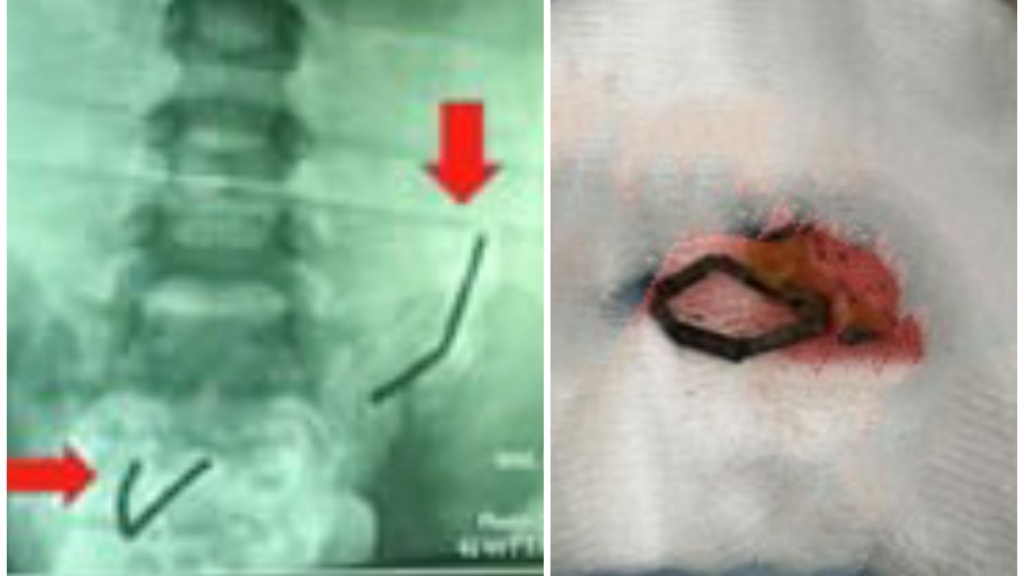

Theo đó, bệnh nhi nam D.T.H (8 tuổi ở huyện Phú Bình, Thái Nguyên) được gia đình cho đi khám và diệt tủy răng ở một cơ sở y tế của huyện. Trong quá trình diệt tủy răng, do bệnh nhi hiếu động nên kim diệt tủy đã rơi vào đường tiêu hóa. Bệnh nhi được chụp X-Quang ổ bụng, thấy có dị vật cản quang. Gia đình đã đưa bệnh nhi đến Bệnh viện Trung ương Thái Nguyên khám và điều trị.

Tại đây, bệnh nhi được gây mê và nội soi thực quản, dạ dày, tá tràng. Kíp nội soi phát hiện kim diệt tuỷ răng nằm dưới khúc III tá tràng. Ngay lập tức, kíp nội soi đã tiến hành can thiệp gắp dị vật ra khỏi tá tràng của bệnh nhi.

Theo BS Nguyễn Hoàng Hà, quá trình nội soi, gắp bỏ chiếc kim ra khỏi tá tràng của bệnh nhi hết sức khó khăn do chiếc kim đã mắc trong ruột khá lâu và sâu. Hơn nữa, do đây là vật sắc nhọn nên nếu không thực hiện cẩn thận có thể gây thủng ruột, nguy hiểm. Sau khi chiếc kim được gắp bỏ ra khỏi cơ thể, sức khỏe bệnh nhi ổn định, bụng mềm, không chướng, không nôn.